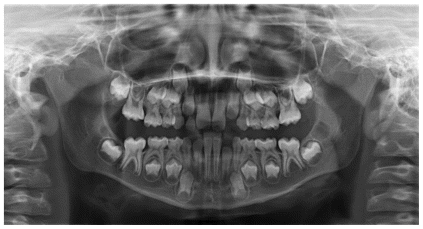

The patient was a 6-year-old female presenting with a Class III dento-skeletal malocclusion associated with anterior crossbite in the early mixed dentition (Figures 20–26). Baseline diagnostic records included orthopantomography, latero-lateral cephalometric radiography with cephalometric analysis, and extraoral and intraoral photographs. Clinical examination revealed a flat-to-slightly convex facial profile with sagittal skeletal discrepancy and negative overjet (Tables 5, 6). The treatment consisted exclusively of functional orthopedic therapy using the AMCOP® TC appliance, worn throughout the night and for one additional hour during the day, for a total duration of 24 months. At the end of active treatment, complete correction of the anterior crossbite was achieved, with normalization of overjet and overbite and establishment of a Class I dental relationship. A long-term follow-up evaluation performed at the age of 12 years, in complete permanent dentition, confirmed the stability of the results, showing a well-maintained anterior dental seal and a stable Class I occlusion. The AMCOP® TC appliance was continued as nighttime retention only, supporting neuromuscular balance and occlusal stability throughout growth.